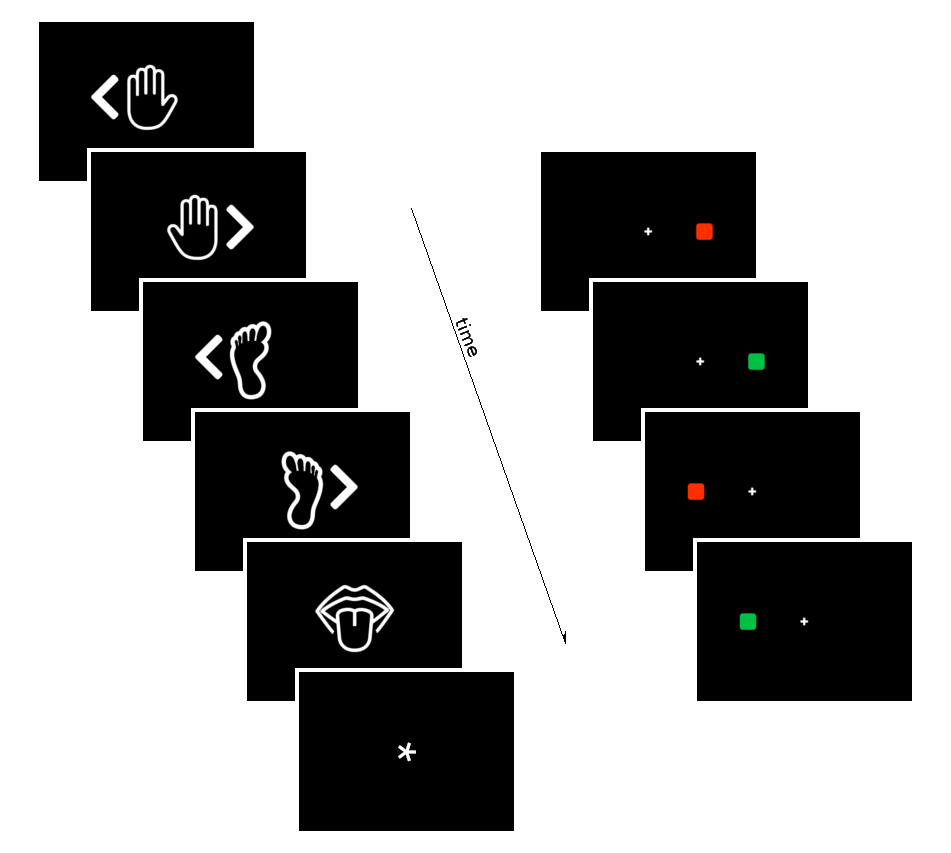

Data

- The first RS of the session

- A motor task

- A Simon task (executive functions)

We preprocessed RS, motor, and Simon data similarly to CVR

We computed:

- RSFA, ALFF, and fALFF from the first RS session

- task Induced Activation (tIA) of Motor task, as each movement vs sham

- tIA of Simon task, considering congruent or incongruent responses

- RSFA, ALFF, and fALFF from the first RS session

- task Induced Activation (tIA) of Motor task, as each movement vs sham

- tIA of Simon task, considering congruent or incongruent responses

We selected:

Methods: effect of CVR on fMRI

Results: CVR, RSF, and tasks

Motor task

Simon task, congruent responses

Simon task, incongruent responses